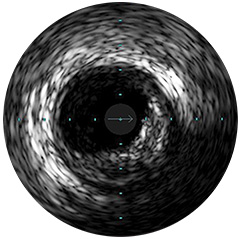

Figura 3